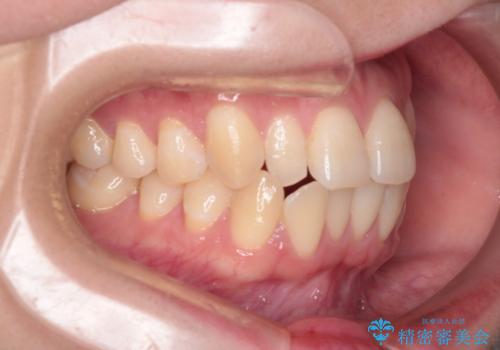

【インビザライン】反対咬合を治したい

- 前歯の反対咬合を主訴に来院されました。

インビザラインにて歯列弓の拡大により叢生の改善を行うことができ、患者様にも満足していただました。

前歯の反対咬合は歯牙への負担も大きくできるだけ早期に治療を行うことを推奨しています。